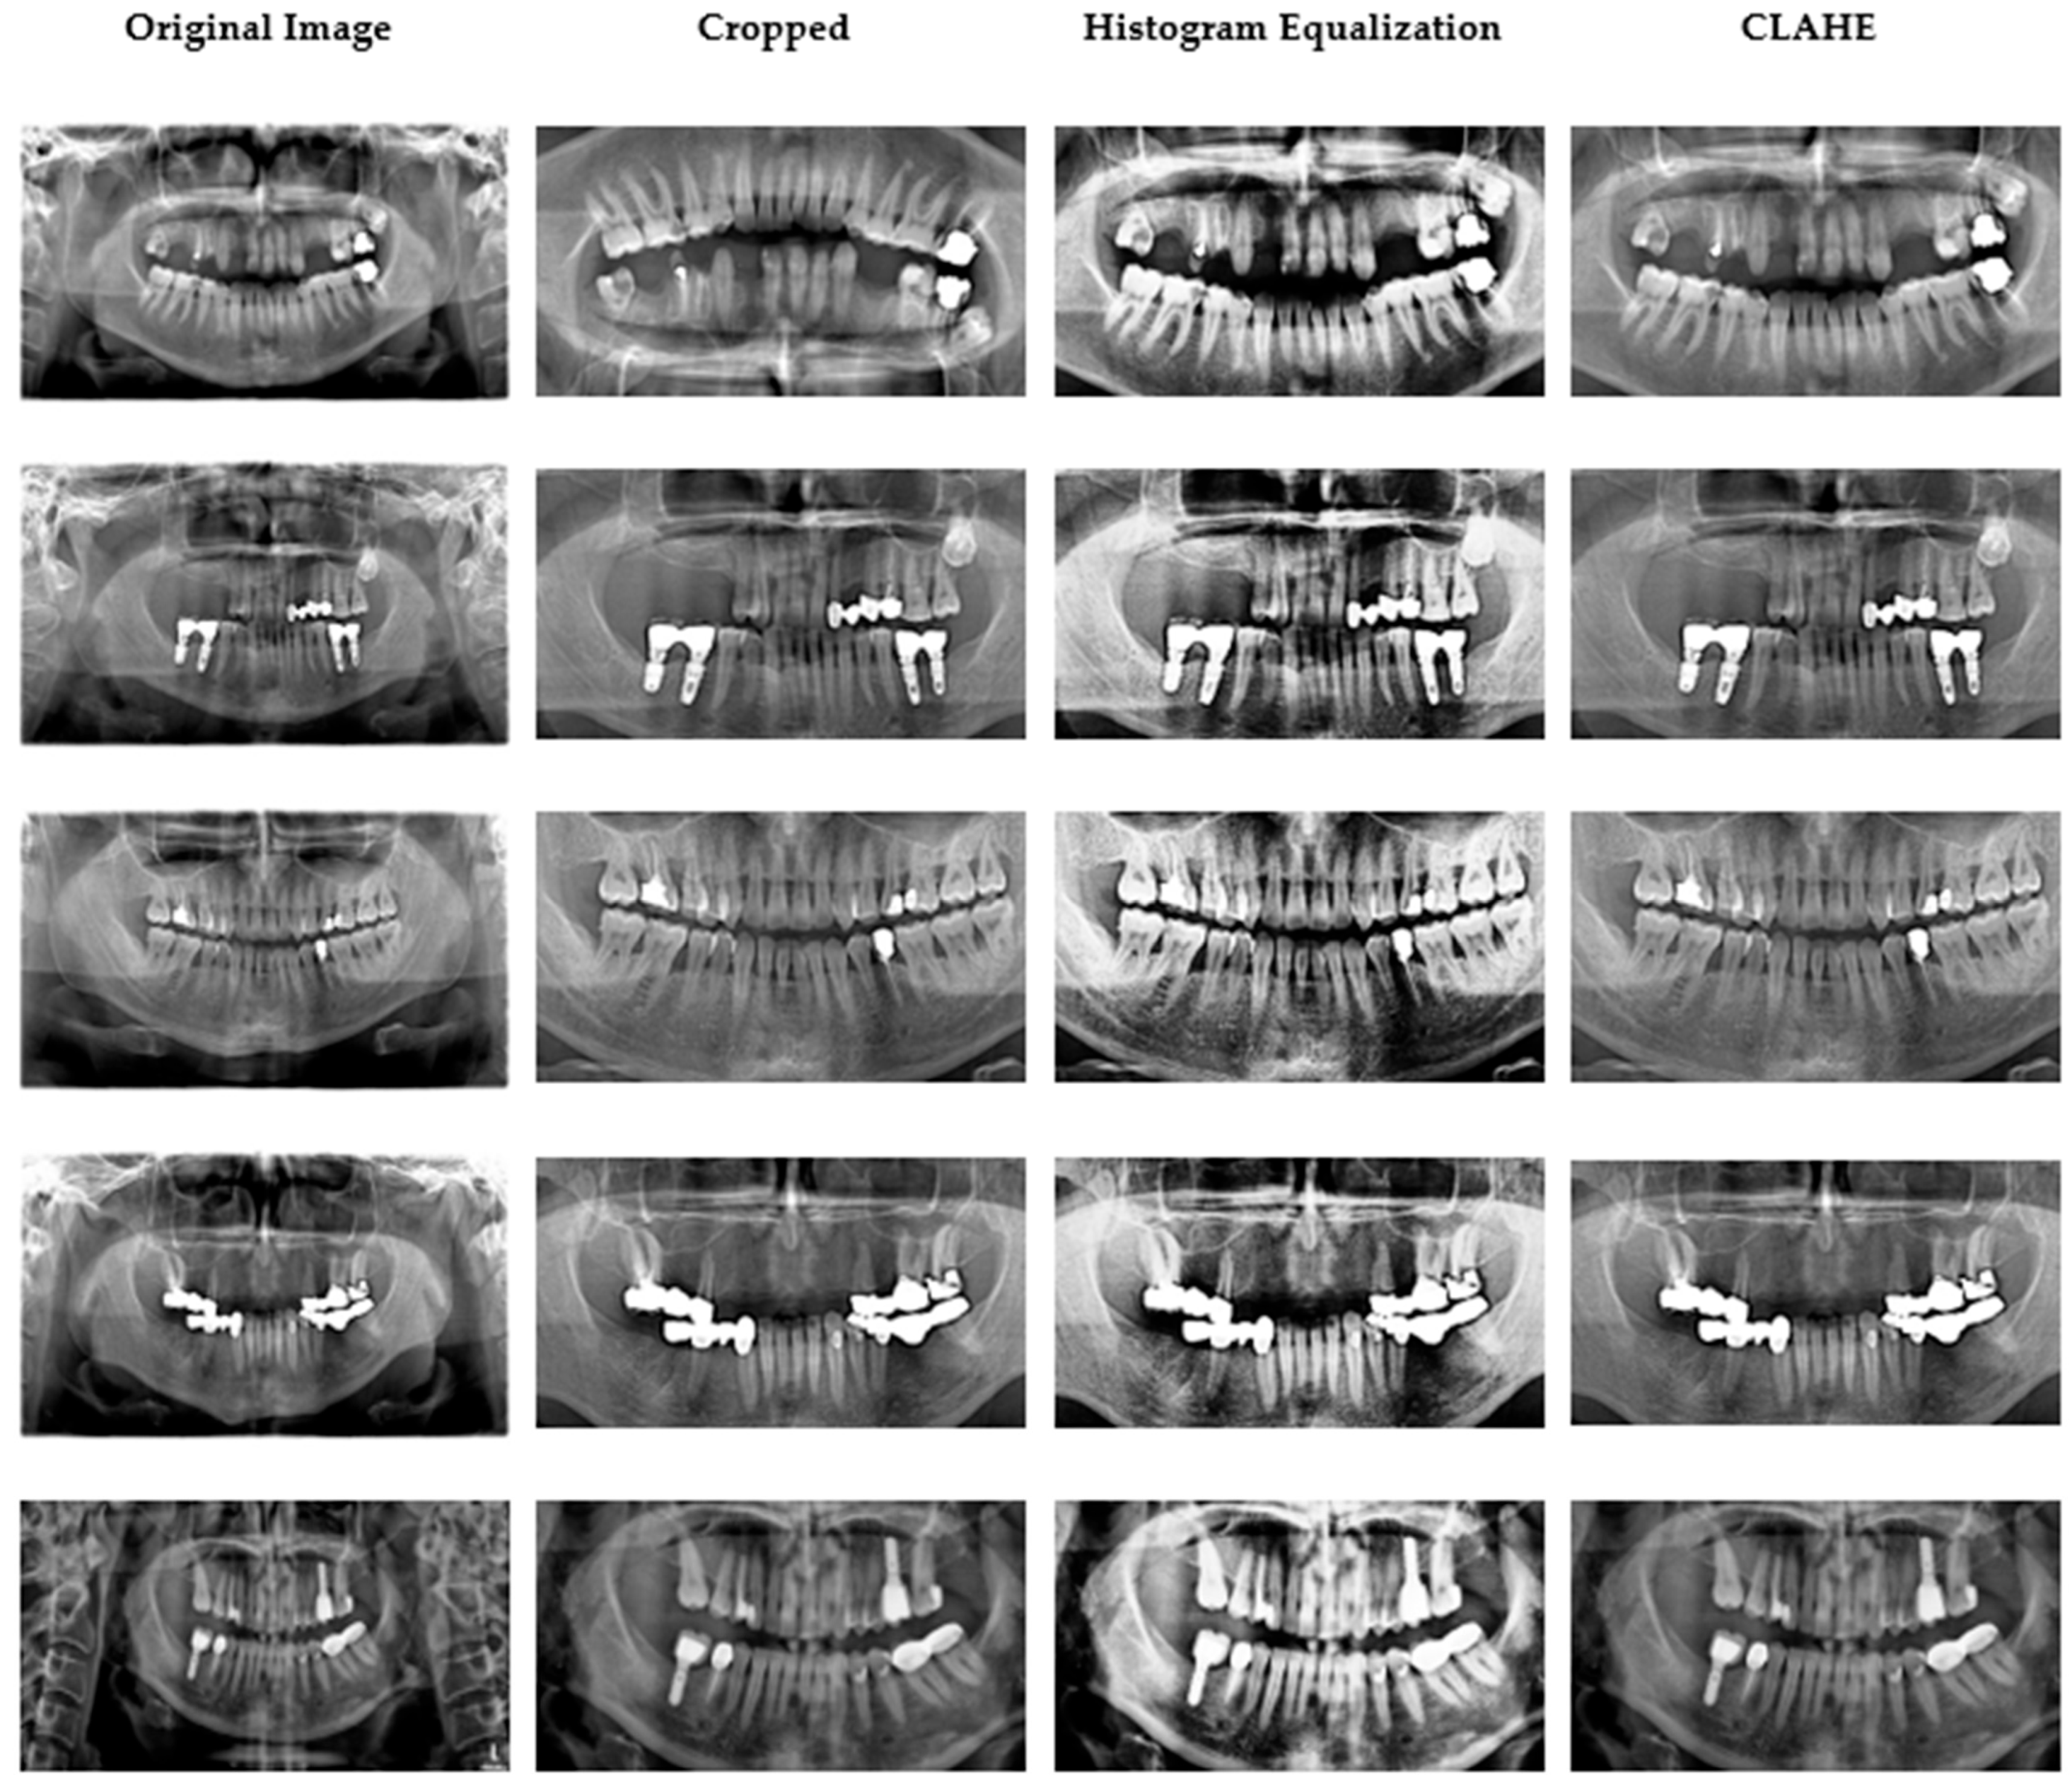

Ethical approval was granted by the Çankırı Karatekin University Ethics Committee (Meeting date: 10 Nov 2023; Meeting no.: 10; Approval ID: 15f61336b5104878). A total of 353 anonymized panoramic radiographs containing 2137 restorations were retrospectively selected from the archives of the Dental Imaging Center in Ankara. All images were acquired using the Orthopantomograph MORITA Veraviewepocs X-550 under identical exposure parameters (70 kVp, 10 mA, 10 s) [21]. The dataset was divided into 80% training and 20% testing on a per-patient basis to prevent leakage across subjects. Each image was independently annotated by two calibrated dentists (one oral radiologist and one prosthodontist). Inter-observer agreement was quantified on 50 randomly chosen cases with a Cohen’s κ = 0.91, indicating excellent reliability [22]. Five restoration categories were defined: filling, implant, root-canal treatment, fixed partial denture (bridge), and crown. Original images (2775 × 1504 pixels) were cropped to 1700 × 880 pixels to exclude non-diagnostic margins. Subsequently, mild global adjustments of contrast, brightness, and color balance were made using the ImageEnhance module of the Python Pillow library. Thereafter, histogram equalization and CLAHE were applied to accentuate differences among restorative materials and surrounding bone structures [23,24]. CLAHE parameters were carefully tuned (clip limit = 2.0, grid size = 8 × 8) to avoid over-processing artifacts [25]. Representative examples of the original image cropped view, and enhanced outputs (histogram equalization and CLAHE) are shown in Figure 2. In pilot ablations on the training folds, applying histogram equalization (HE) followed by CLAHE produced slightly higher validation stability (macro-F1 ≈ +1.5%) compared with either method alone, while preventing over-enhancement. The additional “Pillow smoothing” step was retained only for visual consistency; detailed quantitative ablations will be released with the code for full reproducibility.

Figure 2.

Data samples obtained after image preprocessing.